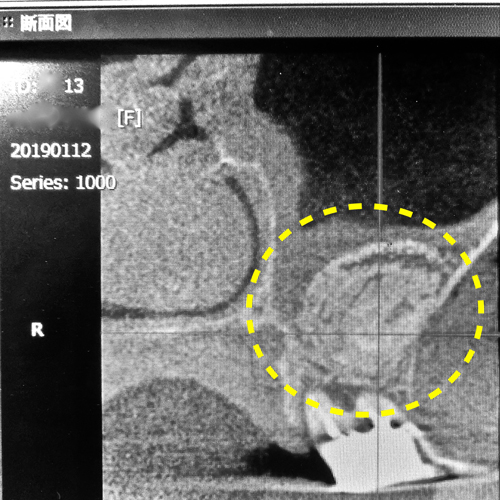

①側面から観たCT画像断面

側面から観たCT画像断面

想像以上に骨がガッチリと出来上がっていました。

手術から3ヶ月後の様子です。